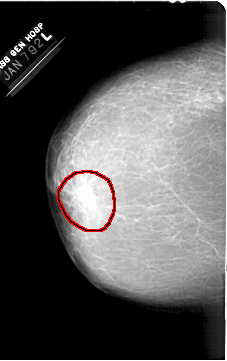

A_1380_1.LEFT_MLO

FILE: A_1380_1.LEFT_MLO.OVERLAY

TOTAL_ABNORMALITIES 1

ABNORMALITY 1

LESION_TYPE MASS SHAPE IRREGULAR MARGINS ILL_DEFINED

ASSESSMENT 4

SUBTLETY 5

PATHOLOGY BENIGN

TOTAL_OUTLINES 1

BOUNDARY